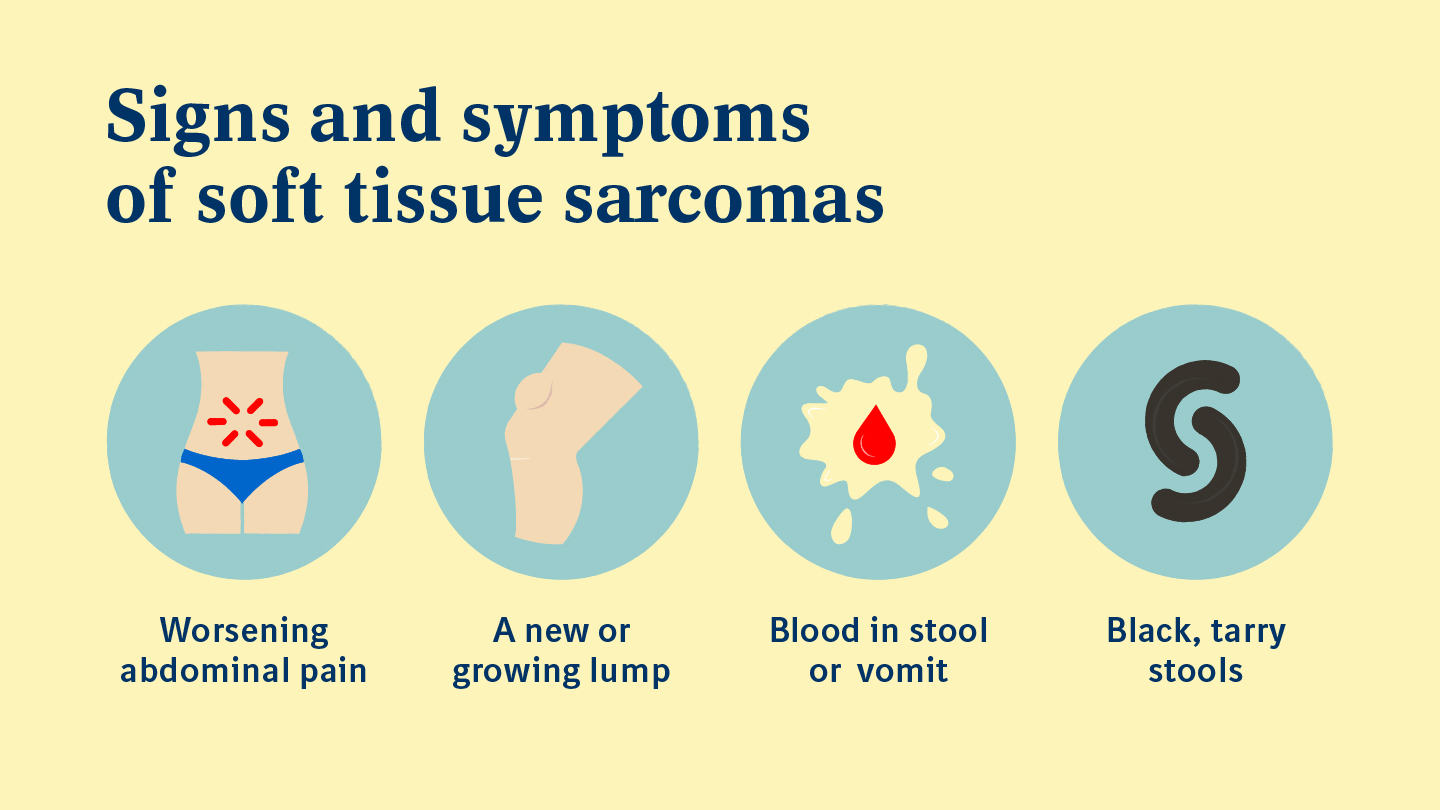

https://www.boehringer-ingelheim.com/sites/default/files/2023-07/BI Oncology_Signs and Symptoms of Sarcoma_Infographic.jpg

Sarcoma An Expert s Perspective Boehringer Ingelheim